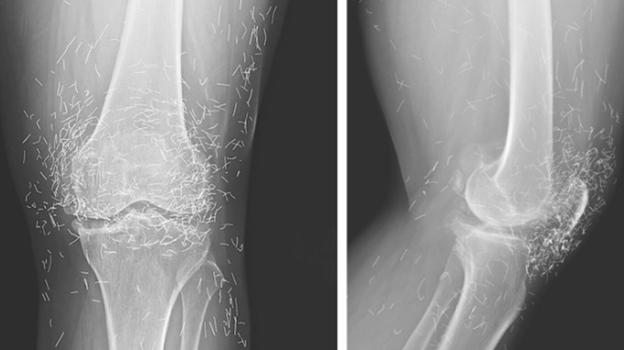

Quello che i dottori hanno visto sullo schermo non era un normale processo di degenerazione ossea, ma qualcosa di assurdo e mai visto prima.

Un’immagine che ha lasciato l’intera equipe medica in uno stato di spavento totale.Le lastre mostravano una condizione talmente estrema che la notizia ha iniziato a fare il giro del mondo in pochi minuti. Non si trattava di una semplice infiammazione, ma di un vero e proprio colpo di scena radiografico che nascondeva un segreto incredibile. Qualcosa di davvero incredibile.